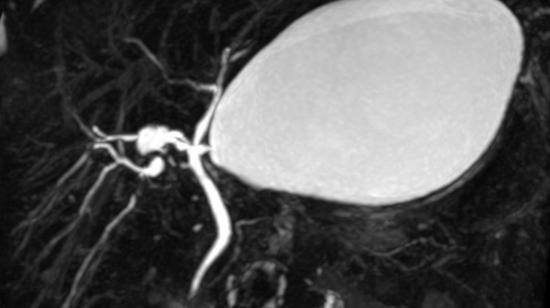

42 years female with right loin pain. On investigation found to have renal Angiomyolipoma. Embolisation of Renal AngiomyolipomaSmaller Angiomyolipomas does not create problems. But they grow very large more than 4 cms in one year. Larger than 5 cms and with aneurysms, pose a ...